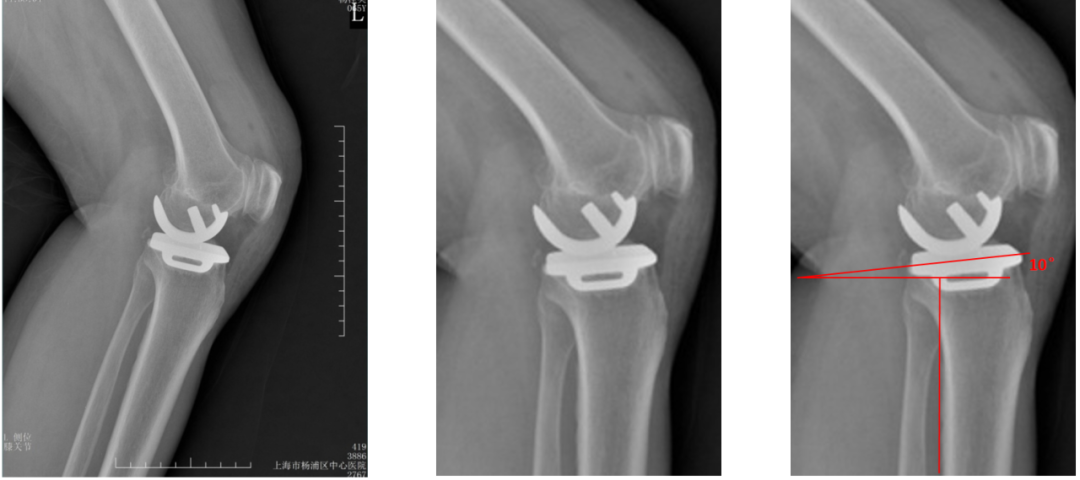

胫骨假体后倾角度(矢状位)

胫骨假体后倾角度:与胫骨侧位中轴线的垂线的最佳夹角 =7°。

胫骨假体后倾角度>7°

胫骨假体后倾角度:与胫骨侧位中轴线(后侧皮质)的垂线的夹角>7°。

胫骨假体后倾角度<7°

胫骨假体后倾角度:与胫骨侧位中轴线(后侧皮质)的垂线的夹角<7°。